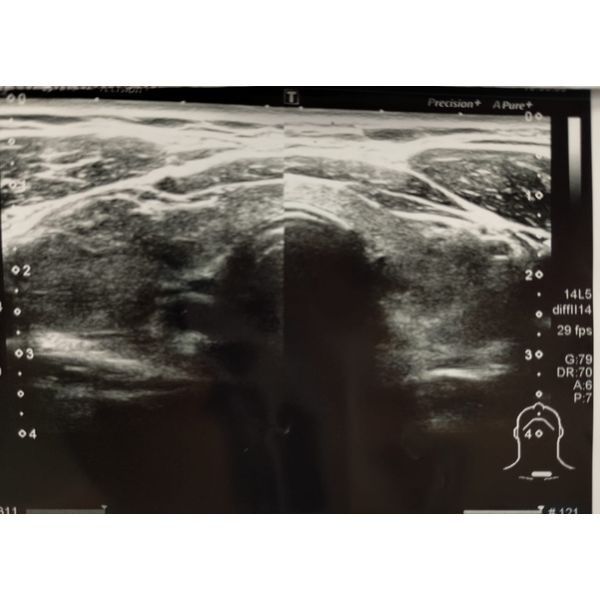

- УЗИ щитовидной железы: объём 45 см3 (выше нормы), узлов нет, кровоток усилен;